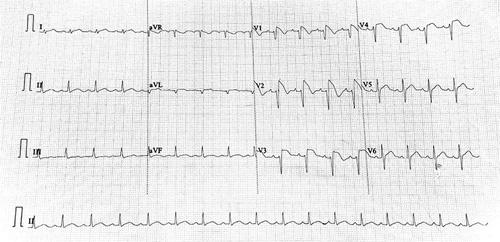

A 22-year-old male presented to the emergency room with a known case of Brugarda pattern ECG with chief complaints of on-and-off abdominal pain and fever for 2 weeks and shortness of breath for one day. On evaluation, echocardiography showed a clot in the inferior vena cava (IVC) and right atrium (RA), and on computed tomography scan of the abdomen revealed a liver abscess with transmural gastric perforation. During, an exploratory laparotomy where a fistula joining the left lobe of the liver and stomach was detected, and an emergency excision was done. The patient was shifted to the ICU and later developed septic shock, which was managed medically.

一名 22 岁男性因已知 Brugada 型心电图被送往急诊室,主要症状为间断性腹痛和发热 2 周,以及气短 1 天。评估时,超声心动图显示下腔静脉(IVC)和右心房(RA)有血栓,腹部计算机断层扫描显示肝脓肿伴胃壁全层穿孔。在剖腹探查术中,发现了连接肝左叶和胃的瘘管,并进行了紧急切除。患者被转入重症监护病房,后来发生感染性休克,经药物治疗。